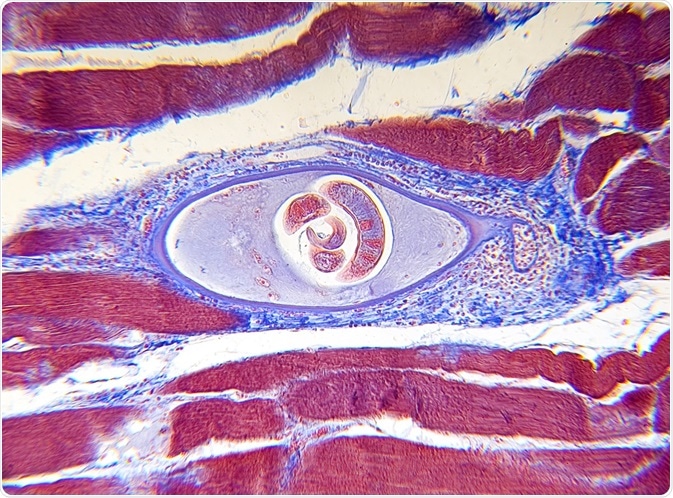

Credit: Carolina K. Smith MD

Trichinellosis is a parasitic zoonotic disease with worldwide distribution, closely related to local dietary and cultural habits. It is caused by nematode species of the genus Trichinella and is usually acquired by the ingestion of raw or undercooked meat containing encysted parasitic larvae.